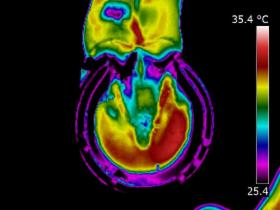

| DISTAL LIMB

| Thermography can point to potential conditions through changes in heat patterns, before the horse shows any clinical signs of injury. It can also reveal hidden signs that other diagnostic tools cannot. It gives us information we didn't know, we didn't know.

| | |  | | | I am very interested in the distal limb and thermography can be used to provide

you and your professional team additional information about conditions such as navicular syndrome,

laminitis, abscesses and corns. Importantly, it can give us information regarding hoof balance and weight-bearing. Hoof balance, often over looked, is a significant influence in the cause of lameness problems not only locally in the foot but throughout the musculature of the body through compensatory issues.